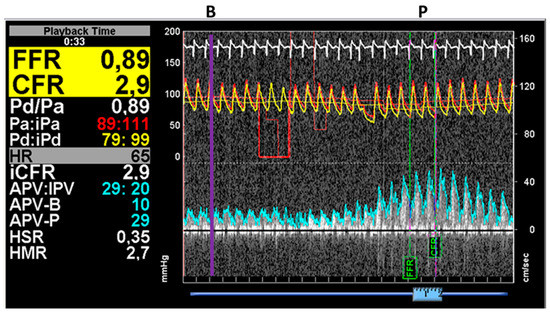

After the pressures were equalized with the sensor positioned at the level of the catheter tip, it was advanced through the coronary artery stenosis, and measurements were performed approximately 2 cm distal to the lesion. Following the basal pressure and flow measurements, 150–200 µg intracoronary adenosine was administered, and the pressure and Doppler traces were recorded. One representative measurement is presented in Figure 2.

Figure 2.

Results of simultaneous pressure and flow measurements by the ComboWire. In this case, the average proximal (aortic) and distal pressures were detected to be 95 mmHg and 88 mmHg, respectively. At maximal hyperemia (P), the average peak velocity (APV-P) increased to 29 cm/s from the basal (B) velocity of 10 cm/s (APV-B) parallel with the increase in the pressure drop (the proximal and distal pressures were 89 mmHg and 79 mmHg, respectively). The measured FFR was 0.89, while the CFR was 2.9 (Case 10).

where bMR: basal microvascular resistance, hMR: hyperemic microvascular resistance and APV-B: basal average peak velocity, APV-P: peak average velocity measured by the ComboWire during basal and hyperemic flow (see Figure 2).